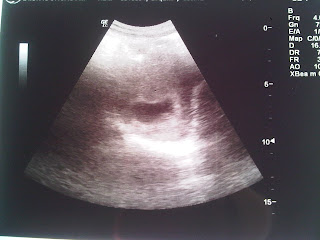

Not so clear. But you can say hye to him/her.

Hye cutie! Assalamualaikum! (^_^)